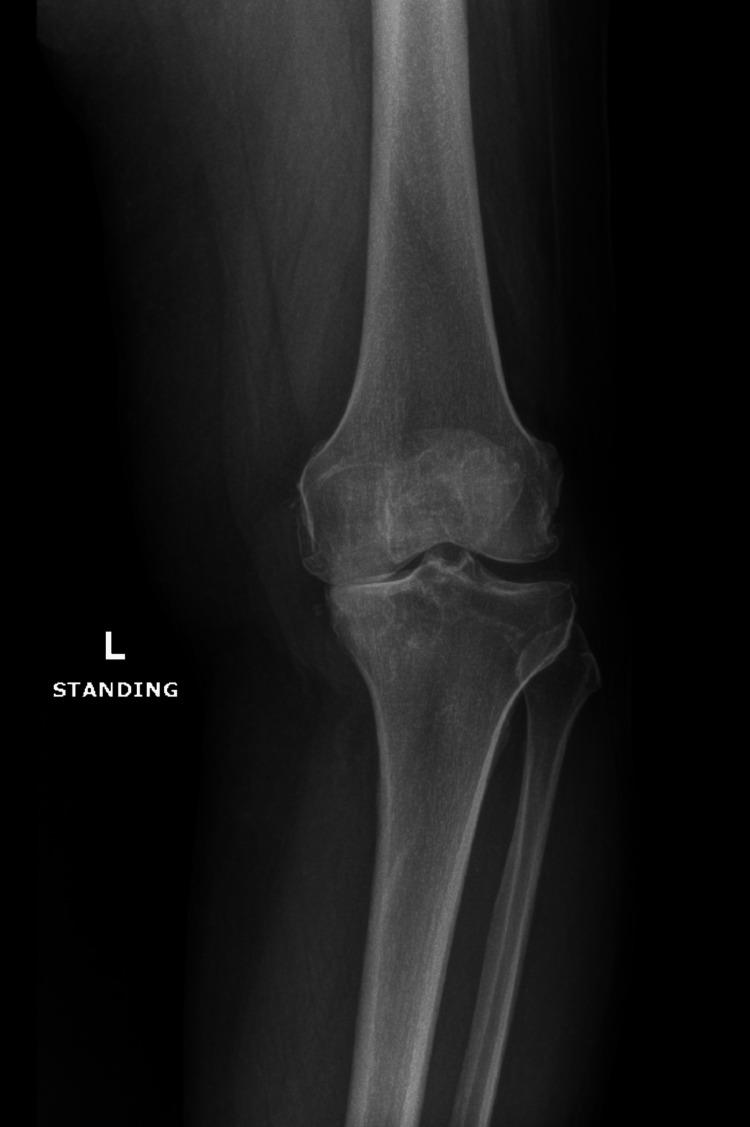

Intraarticular ganglion cysts of the knee are rare, typically incidental findings, and often asymptomatic. However, large cysts may be of clinical interest due to their potential mass effect on surrounding structures. We present the case of a 54-year-old female with a three-year history of osteoarthritis-related knee pain unresponsive to conservative management who ultimately underwent a total knee arthroplasty (TKA). Preoperative imaging revealed a massive, multiloculated intraarticular ganglion cyst extending from Hoffa's fat pad to the medial joint capsule. While the cyst did not interfere with the TKA, its size and location raise important considerations regarding the possible role of intraarticular ganglion cysts in osteoarthritis progression and symptomatology. This case highlights the significance of recognizing and characterizing these lesions and reviewing their potential implications in the setting of advanced knee degeneration.

膝关节内腱鞘囊肿罕见,通常为偶然发现,且常无症状。然而,大囊肿因其对周围结构可能产生的占位效应而具有临床意义。我们报告一例54岁女性病例,该患者有三年与骨关节炎相关的膝关节疼痛病史,保守治疗无效,最终接受了全膝关节置换术(TKA)。术前影像学检查发现一个巨大的、多房性关节内腱鞘囊肿,从Hoffa脂肪垫延伸至内侧关节囊。虽然囊肿未干扰TKA,但它的大小和位置引发了关于关节内腱鞘囊肿在骨关节炎进展和症状学中可能作用的重要思考。该病例强调了识别和描述这些病变以及在晚期膝关节退变情况下审视其潜在影响的重要性。